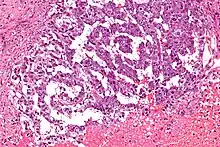

Los tumores vaginales son neoplasias que se encuentran en la vagina. Pueden ser benignos o malignos.[1] Una neoplasia es un crecimiento anormal de tejido que generalmente forma una masa de tejido.[2][3][4] Las neoplasias vaginales pueden ser sólidas, quísticas o de tipo mixto.[5]

Los cánceres vaginales surgen del tejido vaginal, y los sarcomas vaginales se desarrollan a partir de hueso, cartílago, grasa, músculo, vasos sanguíneos u otro tejido conjuntivo o de soporte.[6][7] Los tumores en la vagina también pueden ser metástasis (tejido maligno que se ha diseminado a la vagina desde otras partes del cuerpo).[8][7] El cáncer que se diseminó desde el colon, vejiga y estómago es mucho más común que el cáncer que se origina en la vagina.[9] Algunos tumores benignos pueden progresar hasta convertirse en tumores malignos, como los cánceres vaginales.[10][11] Algunos tumores neoplásicos de la vagina son lo suficientemente raros como para describirse solo en estudios de casos.[3]

Los signos y síntomas pueden incluir una sensación de presión, relaciones sexuales dolorosas o sangrado.[12] La mayoría de los tumores vaginales se localizan durante un examen pélvico. La ecografía, tomografía computarizada y resonancia magnética se utilizan para establecer la ubicación y la presencia o ausencia de líquido en un tumor.[13][14] La biopsia proporciona un diagnóstico más definitivo.[15]